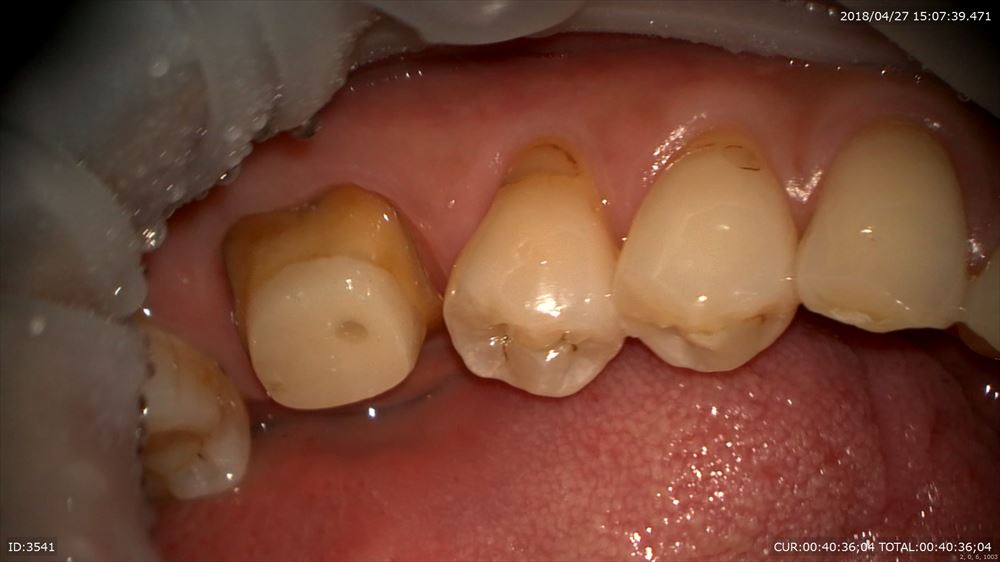

こんにちは。院長の武川です。今日は奥歯にジルコニアのクラウンのセットがありました。

コストパフォーマンスの良い材料で奥歯には私は良く使用します。前歯ですと審美性の観点から(特に透明感が出ない)使用しません。奥歯であれば透明感よりも耐久性の方が優先されます。ですので完璧なフィッティングと強さが優先されたケースの御紹介。

裏側